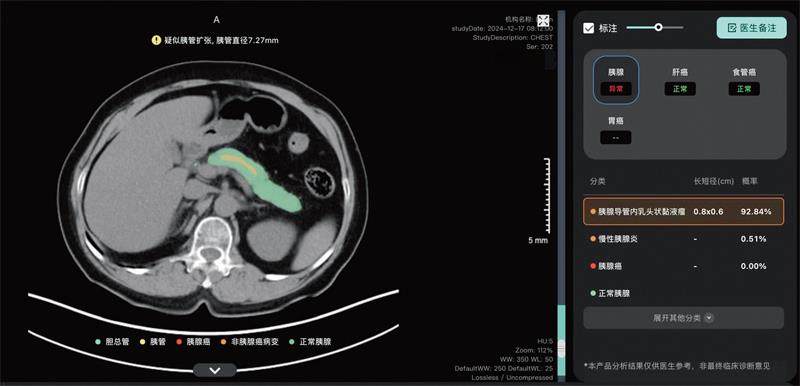

丽水中心医院放射科医生利用AI比照查看病人CT

大模型提示胰腺肿瘤风险

浙江嘉兴的方先生因为咳嗽到浙江省嘉兴市第二医院就诊,其间拍摄了一张胸部平扫CT,常规报告结果显示未见异常。不久后,方先生接到了一通医生的电话:他的CT在医疗AI大模型筛查中提示高度疑似胰腺癌。因为多年体检胰腺都未见异常,方先生的第一反应是:这又是什么新型电信诈骗?但医生解释之后,方先生还是选择回院复查。(剩余2041字)